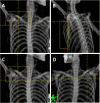

Methods: Sixty-five breast cancer patients who had level II, III axillary or supraclavicular lymph node metastasis on ¹⁸F-FDG PET-CT and received postoperative radiotherapy after modified radical mastectomy were enrolled. One radiation oncologist contoured normal organs (axillary vessels, clavicular head, coracoids process and humeral head) and involved lymph nodes on PET-CT and simulation CT slices. After contouring, deformable image registration of PET-CT on simulation CT was carried out. To evaluate the performance of the DIR, Dice similarity coefficient (DSC) and Center of mass (COM) were used. We created two plans, one was the historically designed three field plan and the other was the modified plan based on the location of axillary lymph node, and we compared the doses that irradiated the axillary lymph nodes.

Results: The DSCs for axillary artery, axillary vein, clavicular head, coracoids process and humeral head were 0.43 ± 0.15, 0.39 ± 0.20, 0.85 ± 0.10, 0.72 ± 0.20 and 0.77 ± 0.20, respectively. The distances between the COMs of axillary artery, axillary vein, clavicular head, coracoids process and humeral head in simulation CT and from PET-CT were 13.0 ±7.1, 20.2 ± 11.2, 4.4 ± 6.3, 3.7 ± 6.7, and 9.5 ± 25.0 mm, respectively. In the historically designed plan, only 57.7% of level II lymph nodes received more than 95% of prescribed dose and the coverage was improved to 70.0% with the modified plan (p < 0.01). For level III lymph nodes, the volumes received more than 95% of prescribed dose were similar in both plans (96.8 % vs 97.9%, p = 0.35).

Conclusion: Deformable image registration of PET-CT on simulation CT was helpful in the identification of the location of the preoperatively involved axillary lymph node. Historically designed three-field plan was not adequate to treat the axillary level II lymph node area. Novel treatment technique based on the location of axillary lymph node from PET-CT using DIR can result in more adequate coverage of nodal area.